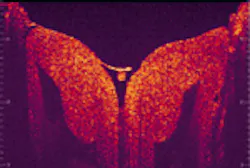

By moving the mirror once the interferometer has extracted the optical signals from the reflected light, the data are processed and high-resolution, cross-sectional (that is, 3-D) digital images of microstructures are produced on an attached computer monitor—all in a matter of seconds. And, because the resolution is so high, the process reveals an enormous amount of data, with the possibility of imaging at the cellular level (see figure). "Optical coherence tomography allows physicians to immediately go beneath the surface of what they are looking at," says Paul Magnin, president of CDT.